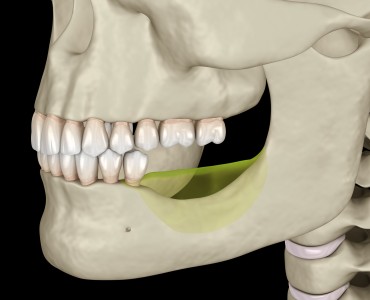

Çene Kemiği Erimesi Nedir? Belirtileri Nelerdir?

Çene kemiği erimesi çeşitli nedenlere bağlı olarak ortaya çıkan ve ilerleyen durumlarda kişinin sağlığını etkileyen bir problemdir.